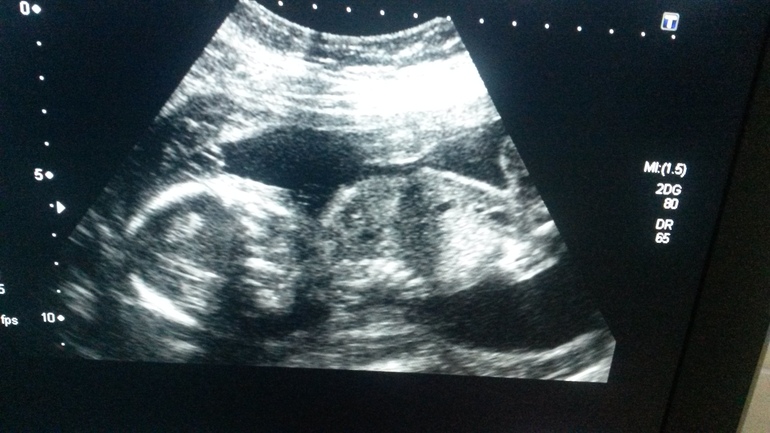

Привет девчонки! Я к вам! Нам 25 неделек. Пока все идет хорошо))ттт.2 скрининг нам показал ангелочка мальчика))) мы безумно рады) малыш во всю пинается, прям футболист какой-то. Весь в папу)) выше фото костюмчика на выписку) думаю в июне будет жарко, поэтому не будем кутать ляльку, куплю позже красивый, легкий вязаный пледик. Беременность 1 я, безумно волнительно на душе. Но надеюсь все будет хорошо))) вот еще фото с узи...фоткала на телефон, Тк делала бесплатно и не о каких фотографиях там речи не могло и быть. Ну хоть что-то) здесь 20 неделек))лежим спинкой